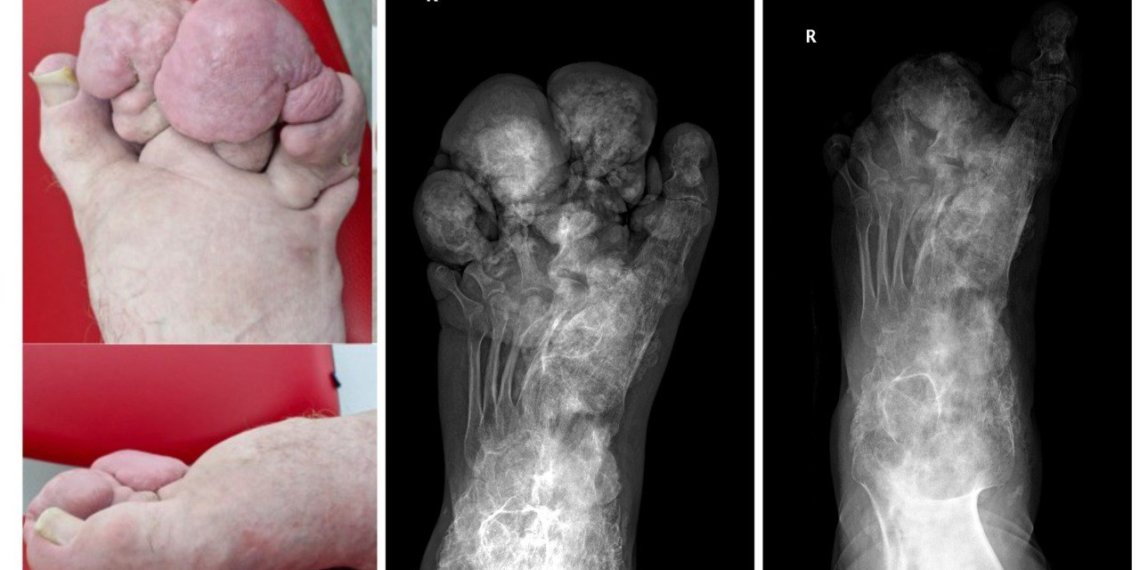

Андрей Кочерыгин страдает синдромом Протея, который вызывает неконтролируемый рост костей, кожи и других тканей. В его случае особенно сильно пострадала правая нога, которая была сильно деформирована и увеличена в объеме из-за патологических костных наростов.

«Костные разрастания были настолько значительными, что ему было трудно наступать на ногу из-за сильной боли, вызванной ущемлением мягких тканей между костными наростами», – рассказал врач-травматолог-ортопед ННИИТО Игорь Пахомов.

Новосибирские хирурги провели сложную операцию по удалению объёмных костных наростов и формированию стопы, близкой к анатомически правильной форме. Впереди еще один этап хирургического лечения, направленный на восстановление подвижности и формы первого пальца стопы.